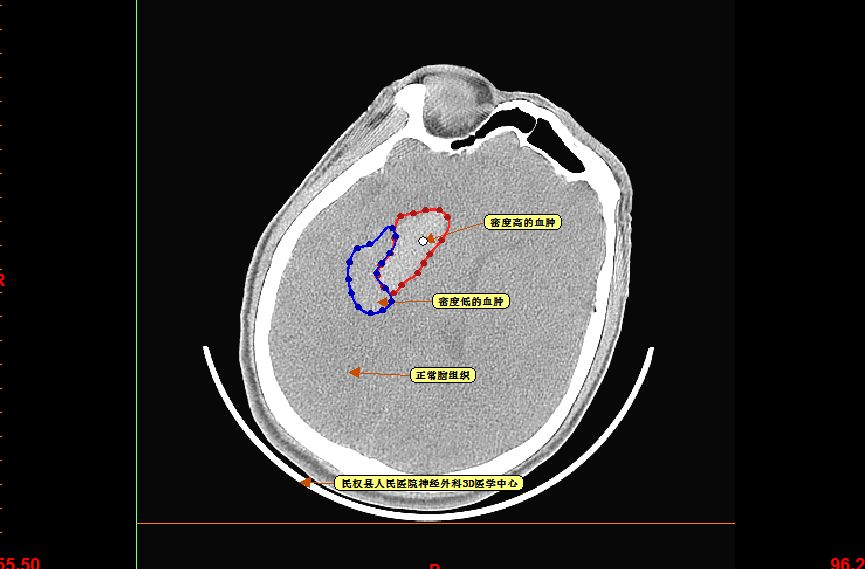

仔细观察CT片可见血肿呈分层现象

再仔细观察并划定血肿分层区域,可设定血肿为高密度区域、低密度区域,和正常脑组织对比

以红色区域划分为高密度区域、蓝色区域划分为低密度区域

测量各密度区域CT阈值,可见高密度区域(红色区域)CT阈值为60.66,低密度区域(蓝色区域)CT阈值为44.39,正常脑组织区域CT阈值为20.94。